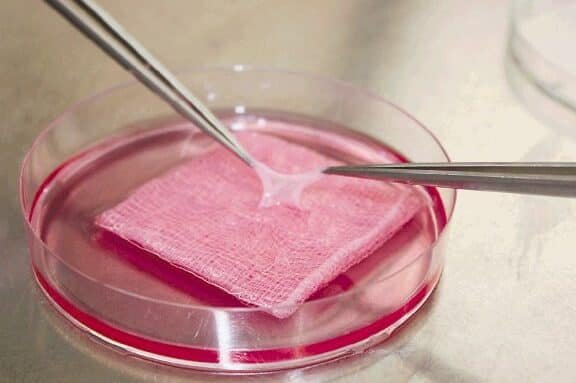

La bioingeniería de tejido hepático para pruebas de toxicidad representa un avance clave en la investigación médica...